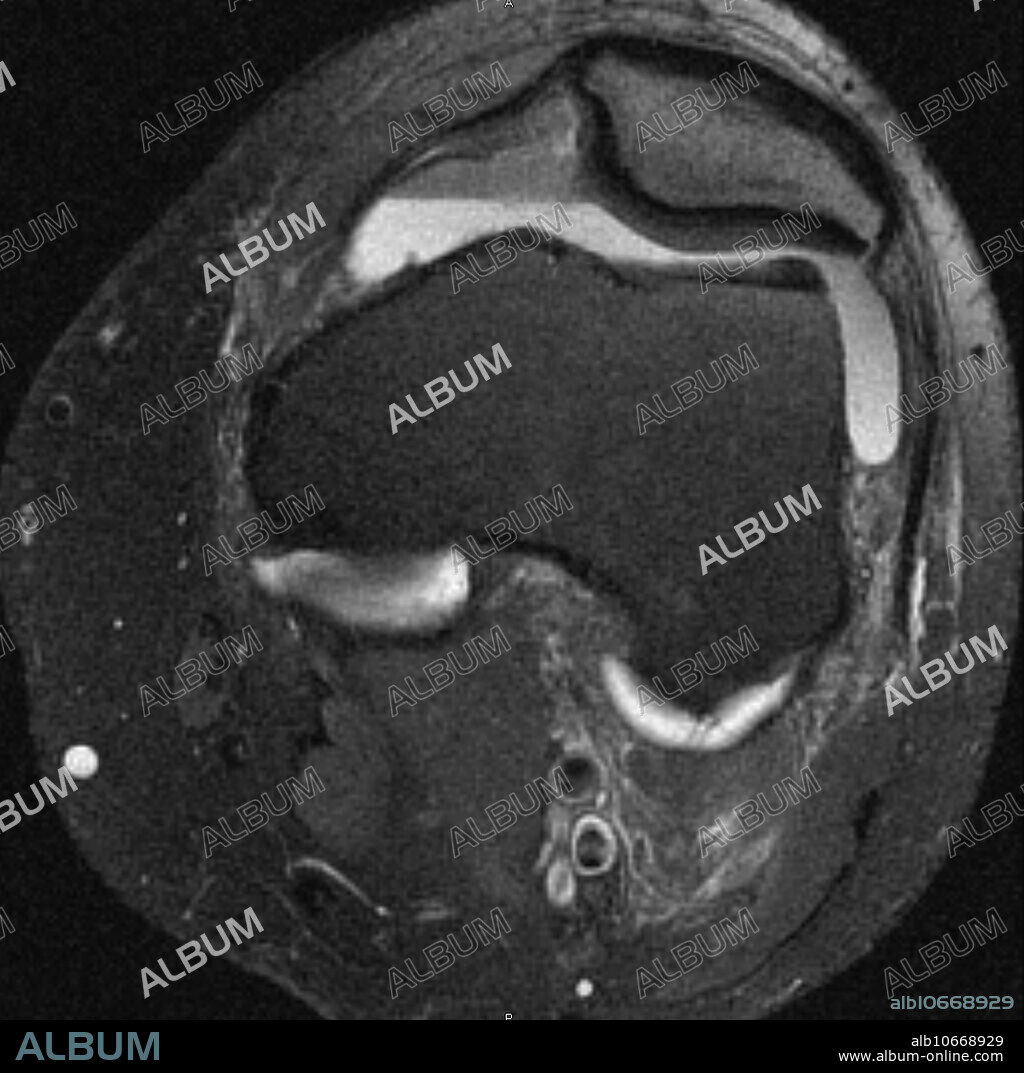

Hemarthrosis, MRI

MRI of knee in 32 year old male with large complicated joint effusion which contains haematocrit fluid blood levels characteristic of hemarthrosis. Complete anterior cruciate ligament tear grade 3 sprain with associated transchondral fractures. Axial fat suppressed T2 weighted image performed on 1.5T high field MRI.